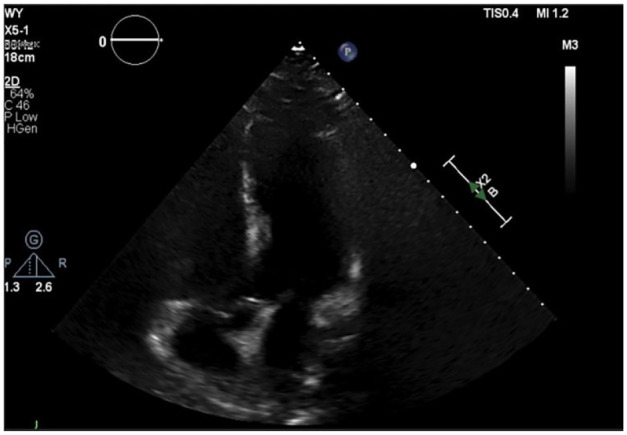

当首次出现时,心电图上的st段抬高需要仔细检查。最令人关注的可能诊断是急性冠状动脉综合征,但它并不是唯一的临床实体,可引起st段抬高。在此,我们报告一例62岁男性吸烟者,既往有未控制的糖尿病、高血压和高脂血症病史,腹痛持续1周。入院时心电图显示st段抬高;然而,他的临床表现,没有心绞痛症状,床边经胸超声心动图正常,肌钙蛋白范围正常,都不是心肌梗死的指示。事实上,他被发现脂肪酶升高,CT结果与急性胰腺炎一致。这个病例强调了一个罕见的胰腺炎的表现,并说明了在评估患者时获得全面的临床病史的重要性,以确保患者得到有效和适当的护理。

When first presented, ST-segment elevation on EKG (electrocardiogram) requires close scrutiny. The most concerning of possible diagnoses is acute coronary syndrome, yet it is not the only clinical entity that can cause ST-segment elevation. Herein, we present a case of a 62-year-old male current smoker with past medical history of uncontrolled diabetes, hypertension, and hyperlipidemia presenting with abdominal pain for 1 week duration. His initial admission EKG illustrated ST-segment elevation; however, his clinical presentation, lack of anginal symptoms, normal bedside transthoracic echocardiogram, and normal range troponin were not indicative of myocardial infarction. In fact, he was found to have elevated lipase and CT findings consistent with acute pancreatitis. This case highlights an uncommon presentation of pancreatitis and illustrates the importance of obtaining a comprehensive clinical history when evaluating patients to ensure patient's receive efficient and appropriate care.